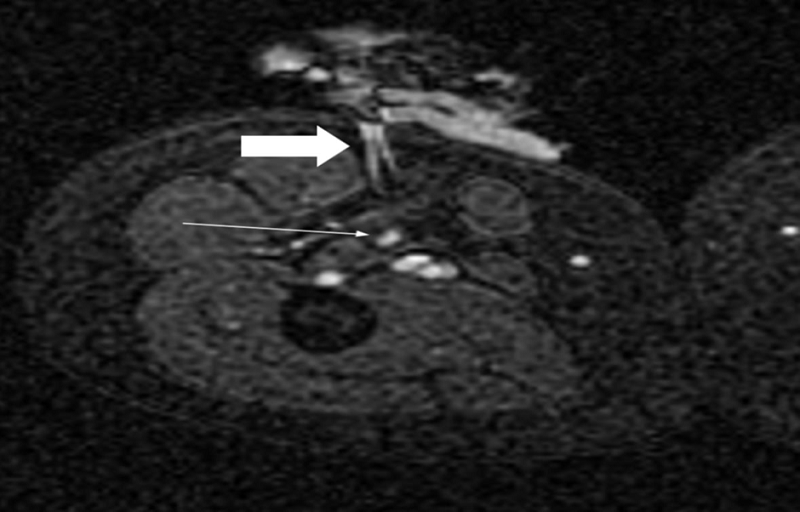

圖:一位78歲肝細(xì)胞癌患者結(jié)合TACE和RFA療法

CBCT是一種多功能工具,可以獨立地執(zhí)行這兩個療法。一些關(guān)于肝細(xì)胞癌和MWA或RFA與TACE聯(lián)合治療的研究表明,它可以改善臨床結(jié)果:特別是,與單獨 TACE 相比,它表現(xiàn)出更長的無進(jìn)展生存期和相當(dāng)?shù)牟l(fā)癥發(fā)生率。在用MWA和腎動脈栓塞治療的一系列T1a腎細(xì)胞癌病例中也記錄了有希望的結(jié)果。然而,還需要進(jìn)一步的研究。